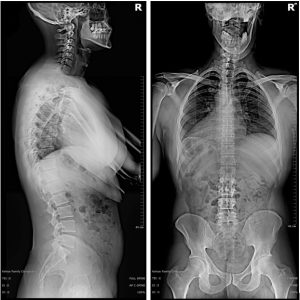

We use state-of-the-art digital x-ray equipment, and when clinically indicated, the use of x-ray imagery can be a very useful tool for Gonstead Chiropractors.

We use state of the art digital x-rays to help assess your condition, determine a treatment plan and rule out any serious pathology.

Involves the use of static palpation, motion palpation, instrumentation (nervoscope – skin temperature differential instrument), visualisation and x-ray analysis.